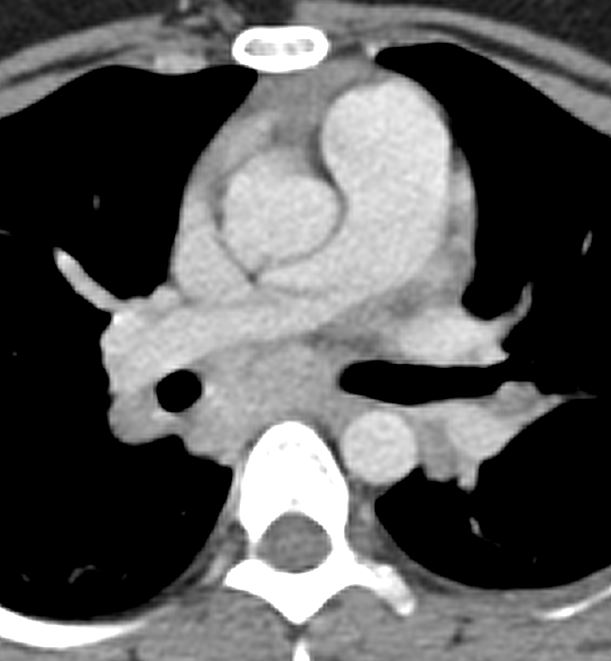

CT pulmonary angiography shows significant partial filling defects involving the right and left pulmonary artery with extension to its lobar branches. Main pulmonary artery to aorta ratio is increased (greater than 1).

Case courtesy of Dr Jeremy Jones, <ahref=”https://radiopaedia.org/”>Radiopaedia.org</a>. From the case <a href=”https://radiopaedia.org/cases/13211″>rID: 13211</a>

The other imaging findings to be mentioned (as they indicate prognosis) are:

- Thrombus burden (subjective)

- Right ventricle: Left ventricle ratio (normal<0.9)

- Changes in bilateral lungs (infarcts)

- Contrast reflux into IVC (due to high pressure in the right atrium).

The most important poor prognostic indicator is increased RV/LV ratio which is a sign RV strain.